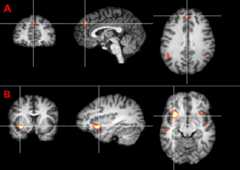

To determine the brain areas that were involved in inhibition of intentional action, we contrasted inhibition trials with action trials. This contrast yielded activation in the dorsal fronto-median cortex (dFMC; Brodmann's area 9) (Fig. 2A), the left and right anterior ventral insula (Fig. 2B), and the right superior temporal sulcus (STS) (Table 1).

Figure 2.

A, Activation in the dFMC for the contrast of inhibition versus action trials. Thez-map is thresholded atz > 3.09 (p < 0.001).B, Activation in the left anterior ventral insula for the contrast of inhibition versus action trials.